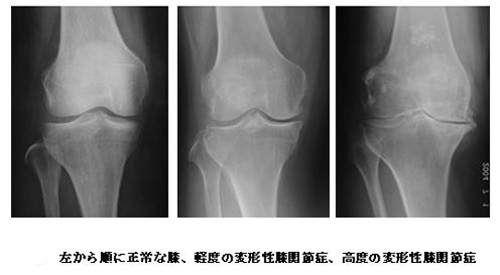

左:正常 中央:変形性膝関節症 右:人工膝関節置換術